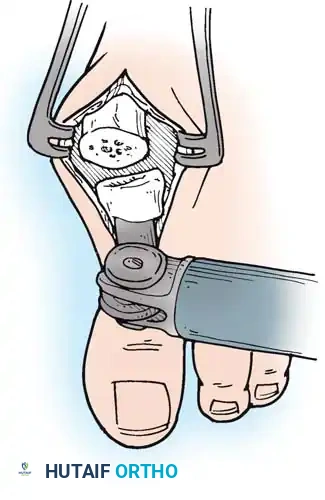

- Resection: The extensor tendons are retracted or lengthened (Z-plasty). The dorsal capsule is opened, and the collateral ligaments are sharply divided to allow plantarflexion of the metatarsal.

- Osteotomy: An oscillating saw is used to resect the metatarsal heads at the anatomical neck. It is imperative to create a smooth, parabolic cascade (the 2nd metatarsal should be the longest, tapering down to the 5th).

- Soft Tissue Balancing: The plantar plate and fat pad, which have migrated distally, are mobilized and pulled proximally under the remaining metatarsal stumps. If the toes remain contracted, closed osteoclasis or PIP joint resection arthroplasties may be performed.

- Pinning: Smooth Kirschner wires (K-wires) are driven antegrade through the toes and retrograde into the metatarsal shafts to hold the toes in neutral alignment.

Intraoperative view demonstrating the exposure and resection of the lesser metatarsal heads to decompress the forefoot and allow reduction of the dislocated digits.